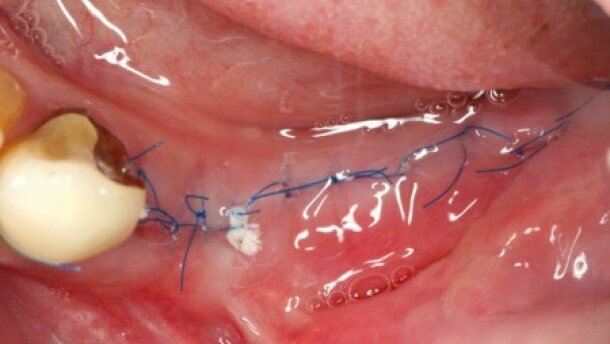

Od wieków w chirurgii wykorzystywane są szwy jedwabne. Są one naturalne i łatwe do zawiązania, a węzły są małe, miękkie i wytrzymałe na rozciąganie.2 Jednak ze względu na plecioną lub skręcaną strukturę, nie są one optymalnym wyborem w środowisku jamy ustnej. Liczne badania wykazały, że użycie szwów jedwabnych oznacza większą penetrację bakterii w głąb rany, a przez to zwiększoną reakcję zapalną i opóźnione gojenie otaczających tkanek.1-5 W badaniach własnych przy użyciu nici jedwabnych (Silk, Resorba; Seraflex, Serag-Wiessner) wykazano tendencję do strzępienia się nici jedwabnych i pozostawania ich fragmentów w tkankach.

Szwy multifilamentowe, niezależnie od resorbowalności, podlegają większej kolonizacji bakteryjnej niż monofilamenty. Powodują tym samym większy odczyn zapalny tkanek i wydłużenie okresu gojenia.1,3,10-12 Parirokh i wsp. badali inwazję bakteryjną struktury szwów jedwabnych i monofilamentu PVDF (fluorek poliwinylidenu), wykonując zdjęcia w mikroskopie skaningowym. Potwierdzili, że penetracja mikroorganizów wzdłuż szwu, w głąb rany zwiększa się wraz z upływem czasu spędzonego w jamie ustnej. W przypadku materiału PVDF, po 3 dniach konglomeraty bakteryjne można było stwierdzić średnio na 6,4% długości szwu, a po 7 dniach na 51%. Jedwabne nici wypadły znacznie gorzej, prezentując obecność bakterii na całej długości już od pierwszych pomiarów (3. dnia badania).13

Wielu autorów opisuje zwiększony stan zapalny i bliznowacenie tkanki po użyciu nici jedwabnych.13,14 Kakoei i wsp. oraz Kim i wsp. porównali reakcje błony śluzowej jamy ustnej na mono- i multifilamenty pod względem histologicznym. Podobnie jak Selvig i wsp. oraz Mirković i wsp., wykazali oni wyższość monofilamentów nad nićmi plecionymi pod względem mniejszej inwazji bakteryjnej i odpowiedzi zapalnej tkanek. Co ciekawe, resorbowalne szwy multifilamentowe (Vicryl) wykazywały podobny stopień zanieczyszczenia mikrobiologicznego i infiltracji komórek układu odpornościowego co szwy jedwabne. (1,3-5)

Ze względu na penetrację i akumulację bakterii wzdłuż włókien szwów plecionych i skręcanych, zwiększają one ryzyko infekcji, wydłużając proces gojenia względem włókiem pojedynczych. Inwazja bakteryjna w głąb tkanek, wzdłuż nici chirurgicznych, wzrasta wraz z wydłużeniem czasu przebywania szwu w tkankach jamy ustnej. W badaniach mikroskopowych oraz ocenie klinicznej lepsze rezultaty gojenia tkanek osiągane są przy użyciu nici monofilamentowych niż multifilamentowych.